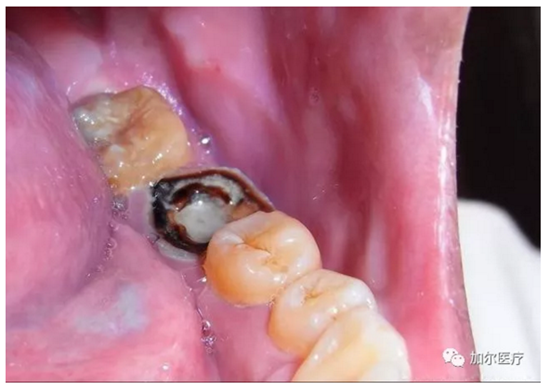

蛀牙連一半的牙冠都沒(méi)了,但是牙齒又不疼,而且還有些發(fā)黑,牙醫(yī)拍片檢查后才知道得做根管治療,那時(shí)牙痛真要人命,可是怎么判斷牙髓壞死?

簡(jiǎn)單來(lái)說(shuō),可以看牙齒表象!觀察顏色是否變黑變暗,實(shí)際上這顆牙齒和死牙沒(méi)什么區(qū)別,不過(guò)比任何假牙好太多了,牙冠再怎么殘缺是一回事,關(guān)鍵自帶天然牙根,只要修復(fù)好和真牙咀嚼功能還是一樣,要不然怎能讓你輕易拔牙呢?